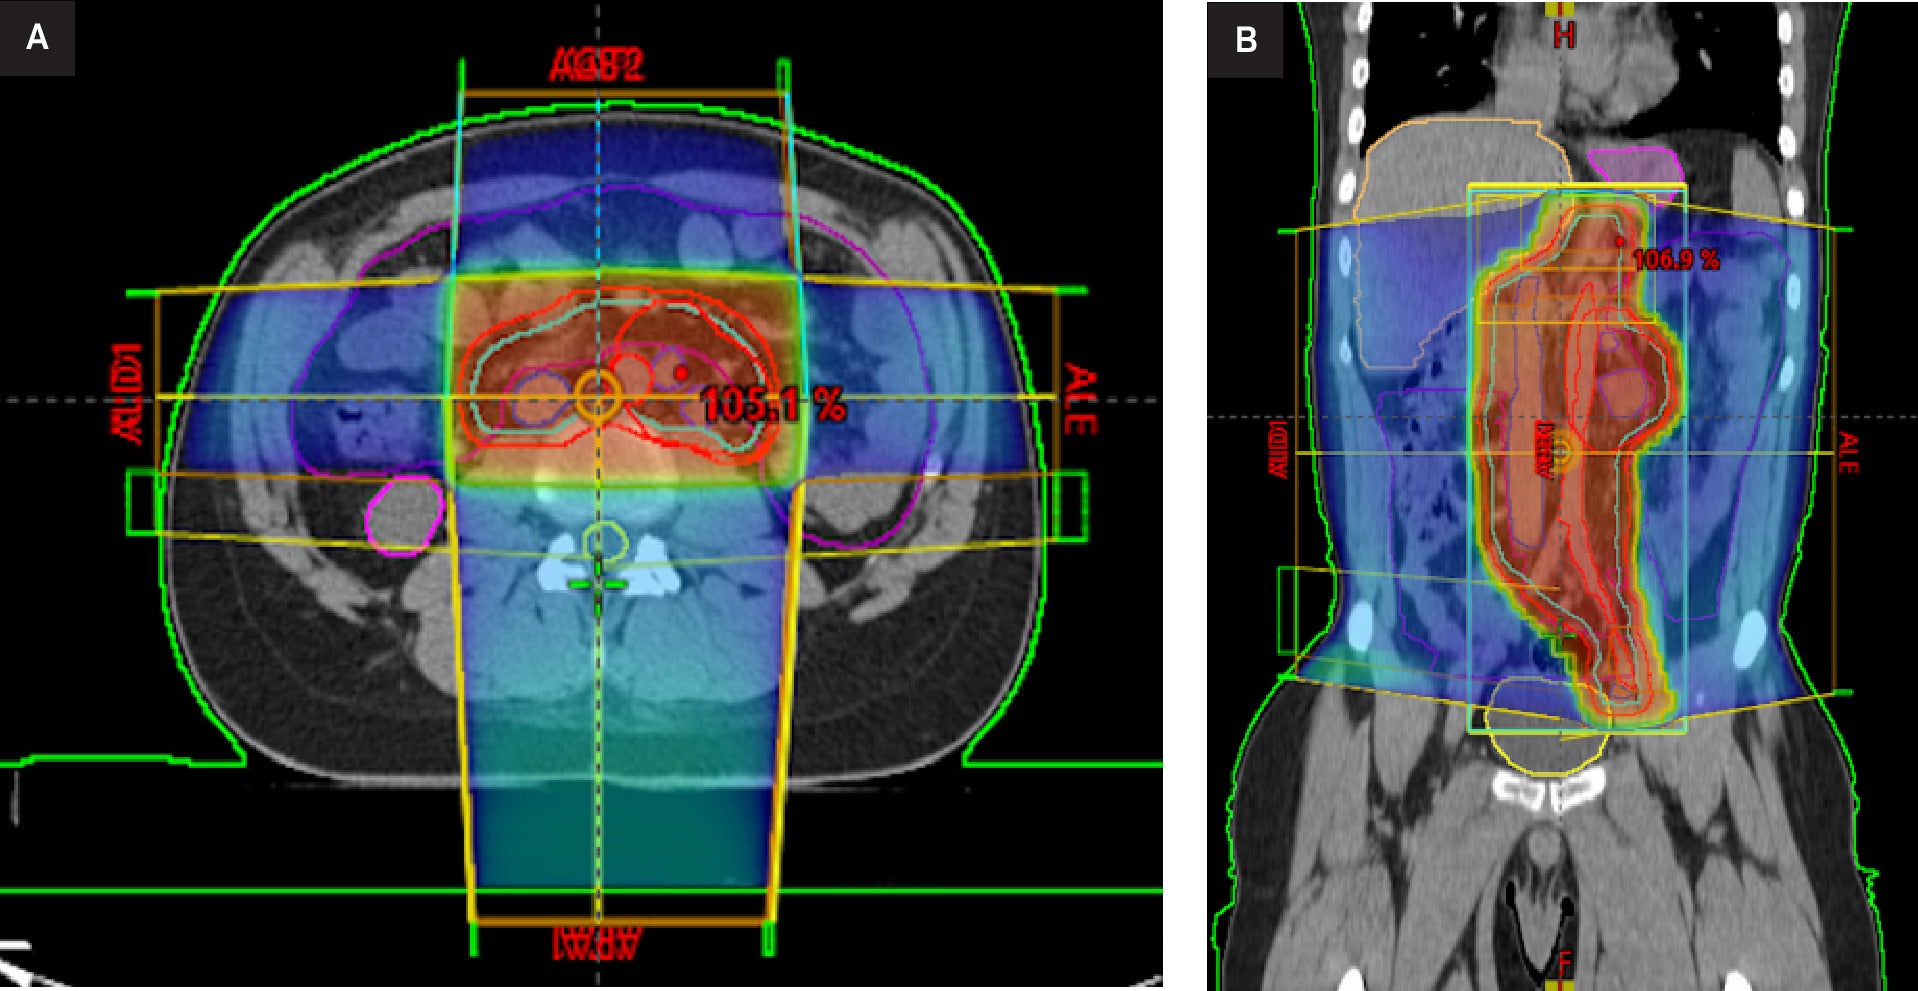

The patient subsequently underwent RT treatment with a 3 DCRT dog-leg technique, receiving a total dose of 20 Gy to the lumboaortic and iliac regions followed by an additional dose (boost) of 16 Gy to the left lateroaortic mass, 2 Gy per fraction, with a total dose of 36 Gy in 18 fractions, once daily (Figure 2). Thoracic organs were outside the field; reported metrics were therefore negligible (mean ≈ 0 Gy, V5 ≈ 0%), eliminating cardiopulmonary exposure. Measures were taken to avoid epileptic spasms, including continuous pulse oximetry, avoidance of hypoxia/hypercarbia, and cardiology oversight. No anesthesia or sedation was required.